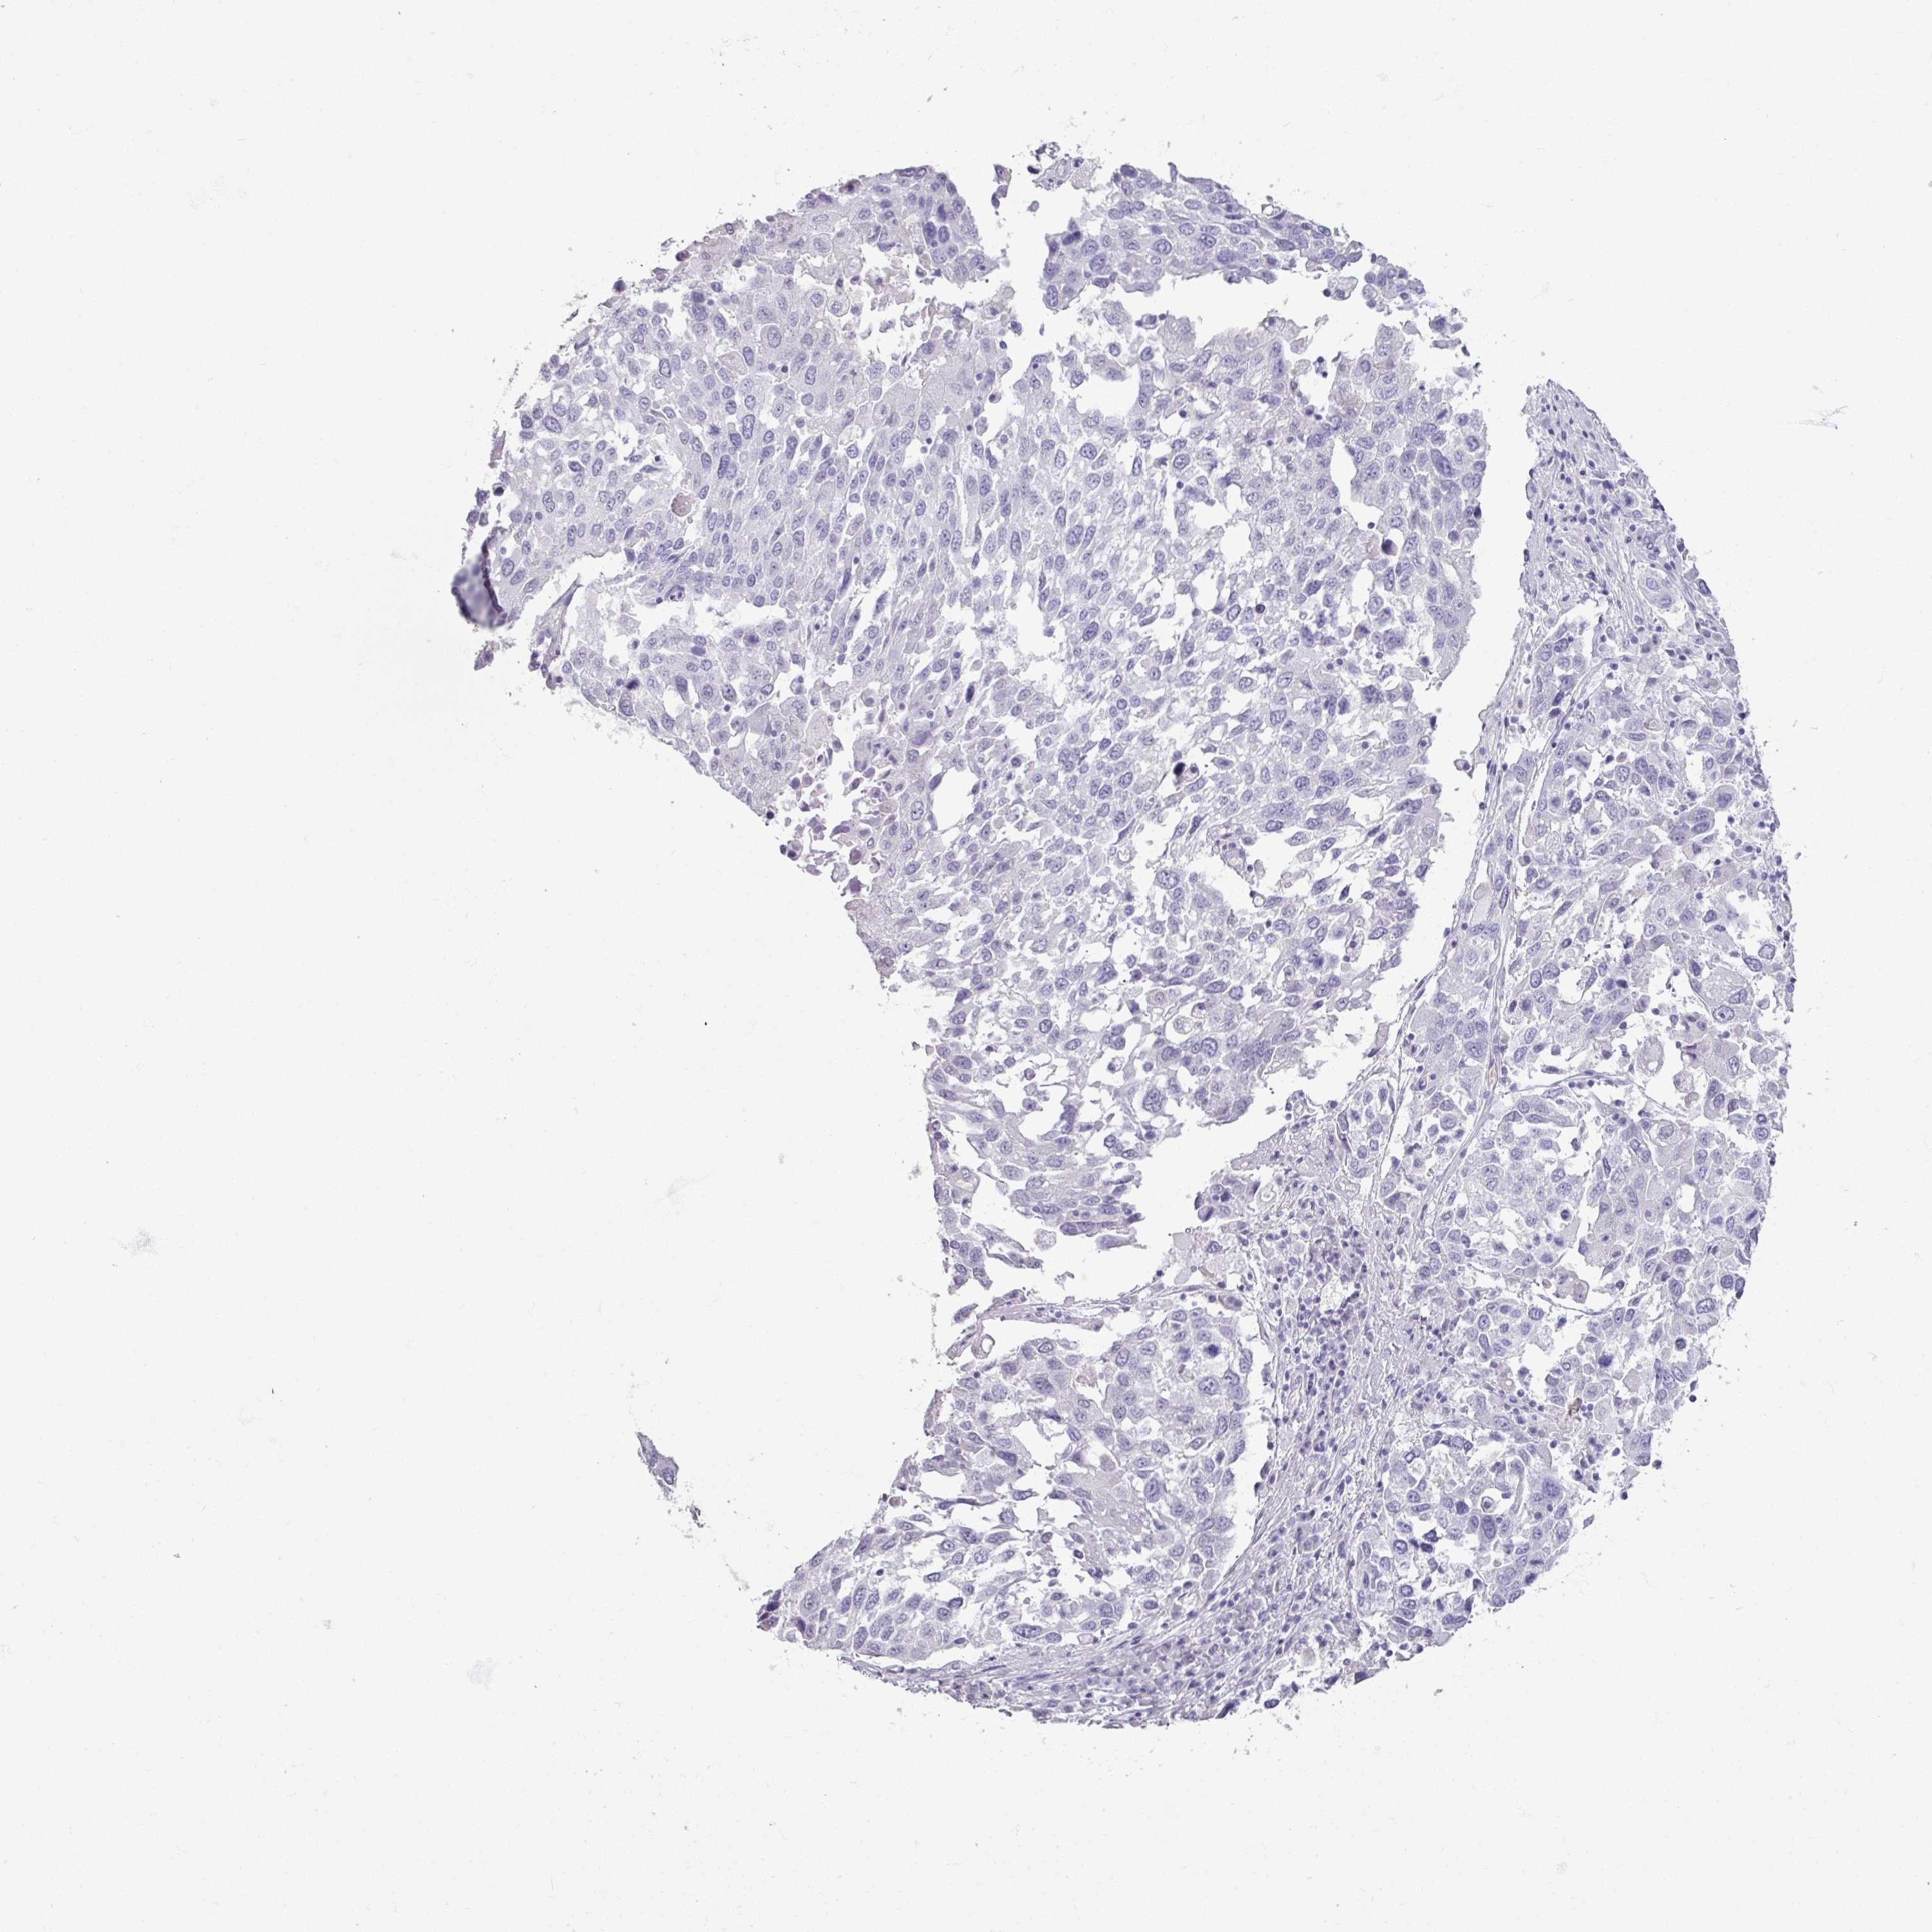

CANCER LUNG CANCER Show tissue menu

LUAD TCGA LUAD VALIDATION LUSC TCGA LUSC VALIDATION PROTEIN LUAD CPTAC PROTEIN LUSC CPTAC PROTEIN EXPRESSION